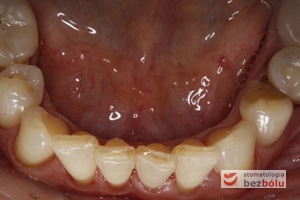

Status dolnego łuku zębowego - mierny stopień zaniku dziąsła- nieliczne wypełnienia przyszyjkowe i okluzyjne

Status dolnego łuku zębowego – mierny stopień zaniku dziąsła- nieliczne wypełnienia przyszyjkowe i okluzyjne

Zęby dolne powierzchnie okluzyjne - brak drugiego przedtrzonowca po stronie prawej - wady zębowe - rotacje i inklinacje

Zęby dolne powierzchnie okluzyjne – brak drugiego przedtrzonowca po stronie prawej – wady zębowe – rotacje i inklinacje